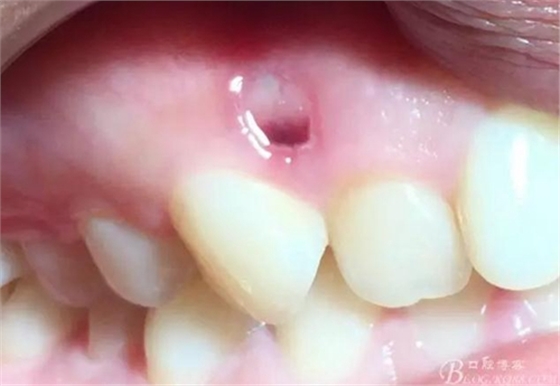

術(shù)后5日

術(shù)后15日

術(shù)后一年

感受:有明確來源性的外源性牙齦色素沉著傳統(tǒng)治療方法有用金剛砂車針磨除著色區(qū)域上皮,或手術(shù)去除著色上皮,或用高頻電刀清除著色上皮,術(shù)后效果無明確預(yù)期,術(shù)中需麻醉,術(shù)后反應(yīng)較大。

激光進(jìn)行牙齦脫色,操作簡(jiǎn)單,效率較高,無需麻醉,患者術(shù)中術(shù)后幾乎無不適反應(yīng),有明確預(yù)期效果。